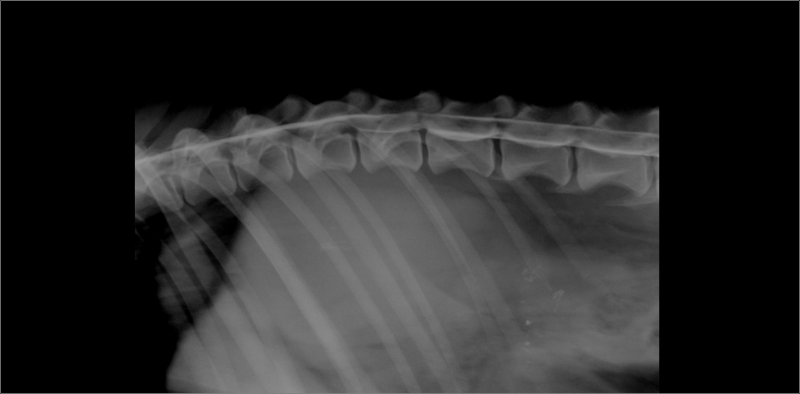

Rib tumor bij hond van 3 jaar .